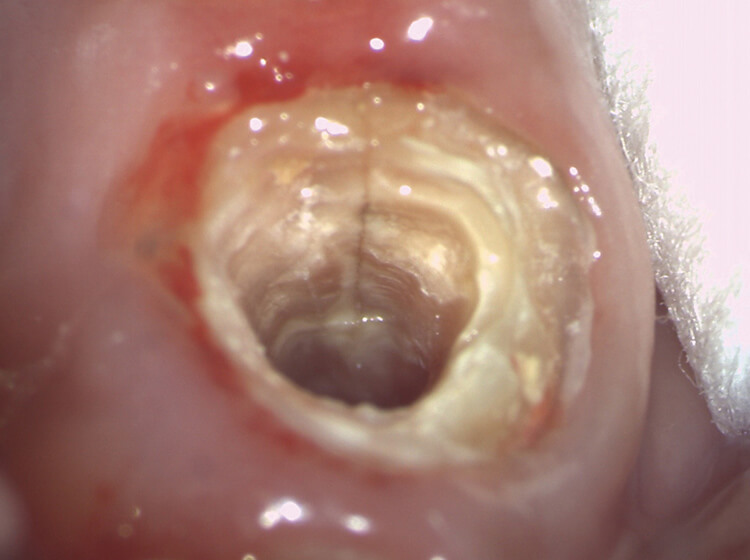

上顎前歯部位に

認める破折線

補綴物脱離にて来院された患者様に患部歯根の状態をきちんと把握して頂くため撮影しました。どの場所にどの深さまでみとめられた破折線なのかが誰が見ても明確で、今後の治療方針の選択にも役立ちます。

写真提供:佐藤道子先生